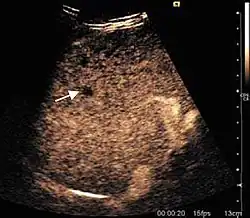

The ultrasound appearance is a well defined lesion, with very thin, almost unapparent walls, without circulatory signal at Doppler or CEUS investigation. The content is transonic suggesting fluid composition. The presence of membranes, abundant sediment or cysts inside is suggestive for parasitic, hydatid nature. Posterior from the lesion the acoustic enhancement phenomenon is seen, which strengthens the suspicion of fluid mass. They typically displace normal liver vessels but no vascular or biliary invasion occurs.

-

Liver cyst -